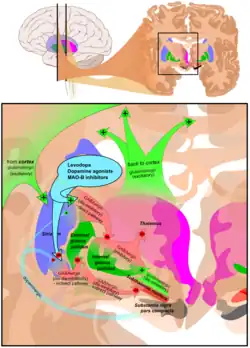

The main families of drugs useful for treating motor symptoms are levodopa, dopamine agonists, and MAO-B inhibitors.[3] The most commonly used treatment approach varies depending on the disease stage. Two phases are usually distinguished: an initial phase in which the individual with PD has already developed some disability which requires pharmacological treatment, and a second stage in which the patient develops motor complications related to levodopa usage.[3] Treatment in the initial state aims to attain an optimal tradeoff between good management of symptoms and side effects resulting from enhancement of dopaminergic function. The start of L-DOPA treatment may be delayed by using other medications such as MAO-B inhibitors and dopamine agonists, in the hope of delaying the onset of dyskinesias.[3] In the second stage, the aim is to reduce symptoms while controlling fluctuations of the response to medication. Sudden withdrawals from medication, and overuse by some patients, also must be controlled.[3] When medications are not enough to control symptoms, surgical techniques such as deep brain stimulation can relieve the associated movement disorders.[4]

Levodopa (or L-DOPA) has been the most widely used treatment for over 30 years.[3] L-DOPA is transformed into dopamine in the dopaminergic neurons by dopa-decarboxylase.[3] Since motor symptoms are produced by a lack of dopamine in the substantia nigra, the administration of L-DOPA temporarily diminishes the motor symptoms.[3]

Monoamine oxidase inhibitors (selegiline and rasagiline) increase the level of dopamine in the basal ganglia by blocking its metabolization. They inhibit monoamine oxidase-B (MAO-B) which breaks down dopamine secreted by the dopaminergic neurons. Therefore, reducing MAO-B results in higher quantities of L-DOPA in the striatum.[3] Similarly to dopamine agonists, MAO-B inhibitors improve motor symptoms and delay the need of taking levodopa when used as monotherapy in the first stages of the disease, but produce more adverse effects and are less effective than levodopa. Evidence on their efficacy in the advanced stage is reduced, although it points towards them being useful to reduce fluctuations between on and off periods.[3] Although an initial study indicated selegiline in combination with levodopa increased the risk of death, this has been later disproven.[3]